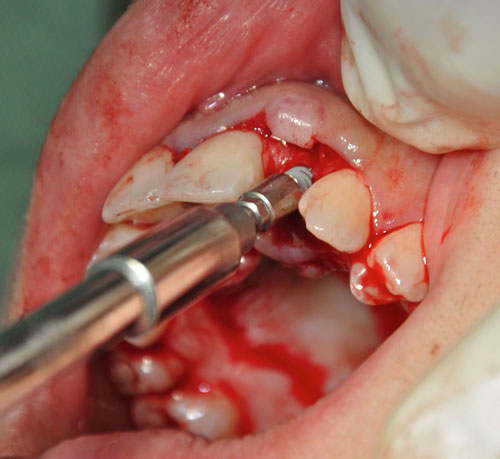

Abordamos con fresa lanceolada para el marcaje del lecho y expandimos con expansores roscados para densificar un hueso de Tipo IV

Realizamos un colgajo vestibular y palatino sin incisión de descarga para preservar lo mas posible el aporte sanguíneo

Instalación de implantes

Instalación de implantes

Instalación de implantes

Instalación de implantes